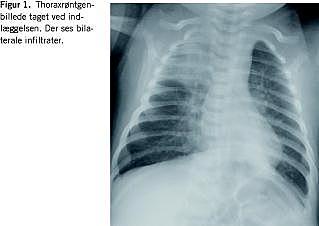

Der blev foretaget røntgenundersøgelser af thorax som viste bilaterale infiltrater (Figur 1 ). C-reaktivt protein var ved indlæggelsen 143, men faldt til 60 efter påbegyndelse af antibiotikabehandling. Siden steg det imidlertid til 165. Normalværdi < 10. Leukocytter fandtes at være 29,5 × 106 med lymfocytose, men steg siden til 100 × 106 . Dyrkning af trakealsekret viste ingen patogene fund. Bordetella pertussis blev verificeret ved polymerasekædeundersøgelse af trakealsekretet.